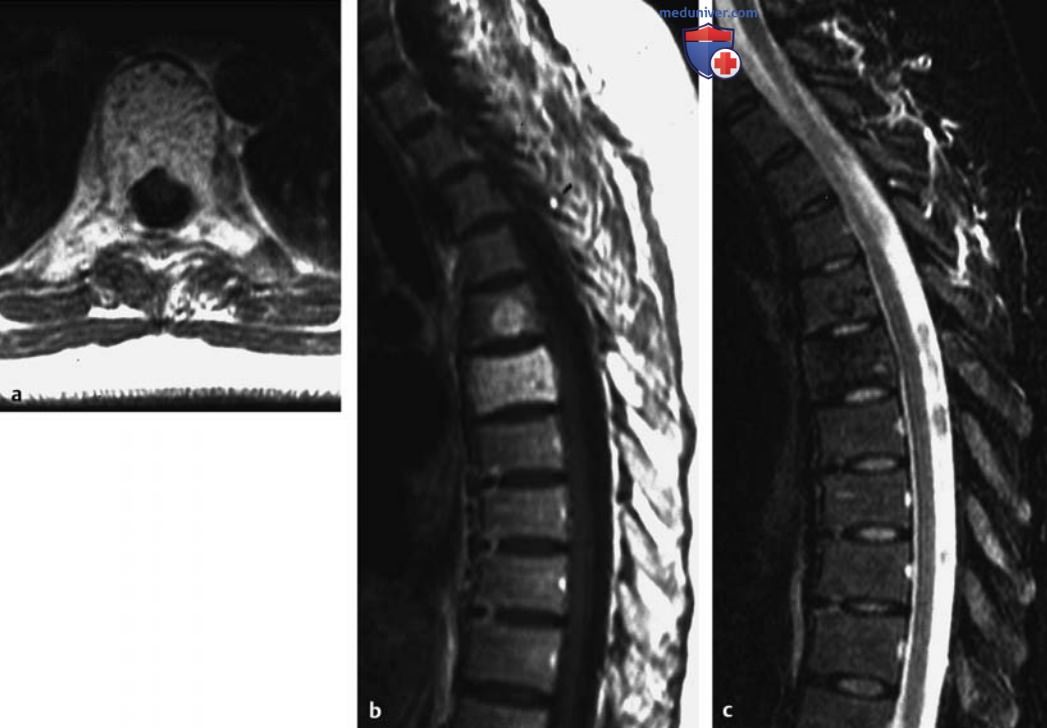

Рисунок 1. а-c Кортикальная остеоид-остеома большеберцовой кости.

а Т1в-SE-изображение в сагиттальной плоскости.

b Т2в-SE-изображение в аксиальной плоскости.

c Т1в-SE-изображение с контрастированием. Нидус диаметром примерно 4 мм (стрелки) виден в заметно утолщенном кортикальном слое диафиза большеберцовой кости. На аксиальном срезе отмечается реактивный отек костного мозга, а также периостальный и параостальный отек мягких тканей, окружающий большеберцовую кость (головки стрелок).

- Типичными признаками являются регионарный отек костного мозга и отек мягких тканей, который может окружать кость (см. рис. 1). Эти признаки могут выявляться при использовании STIR, на Т2в-изображениях со спектральным подавлением сигнала от жировой ткани и на Т1в-изображениях после контрастирования и могут быть ошибочно интерпретированы как проявление злокачественности.